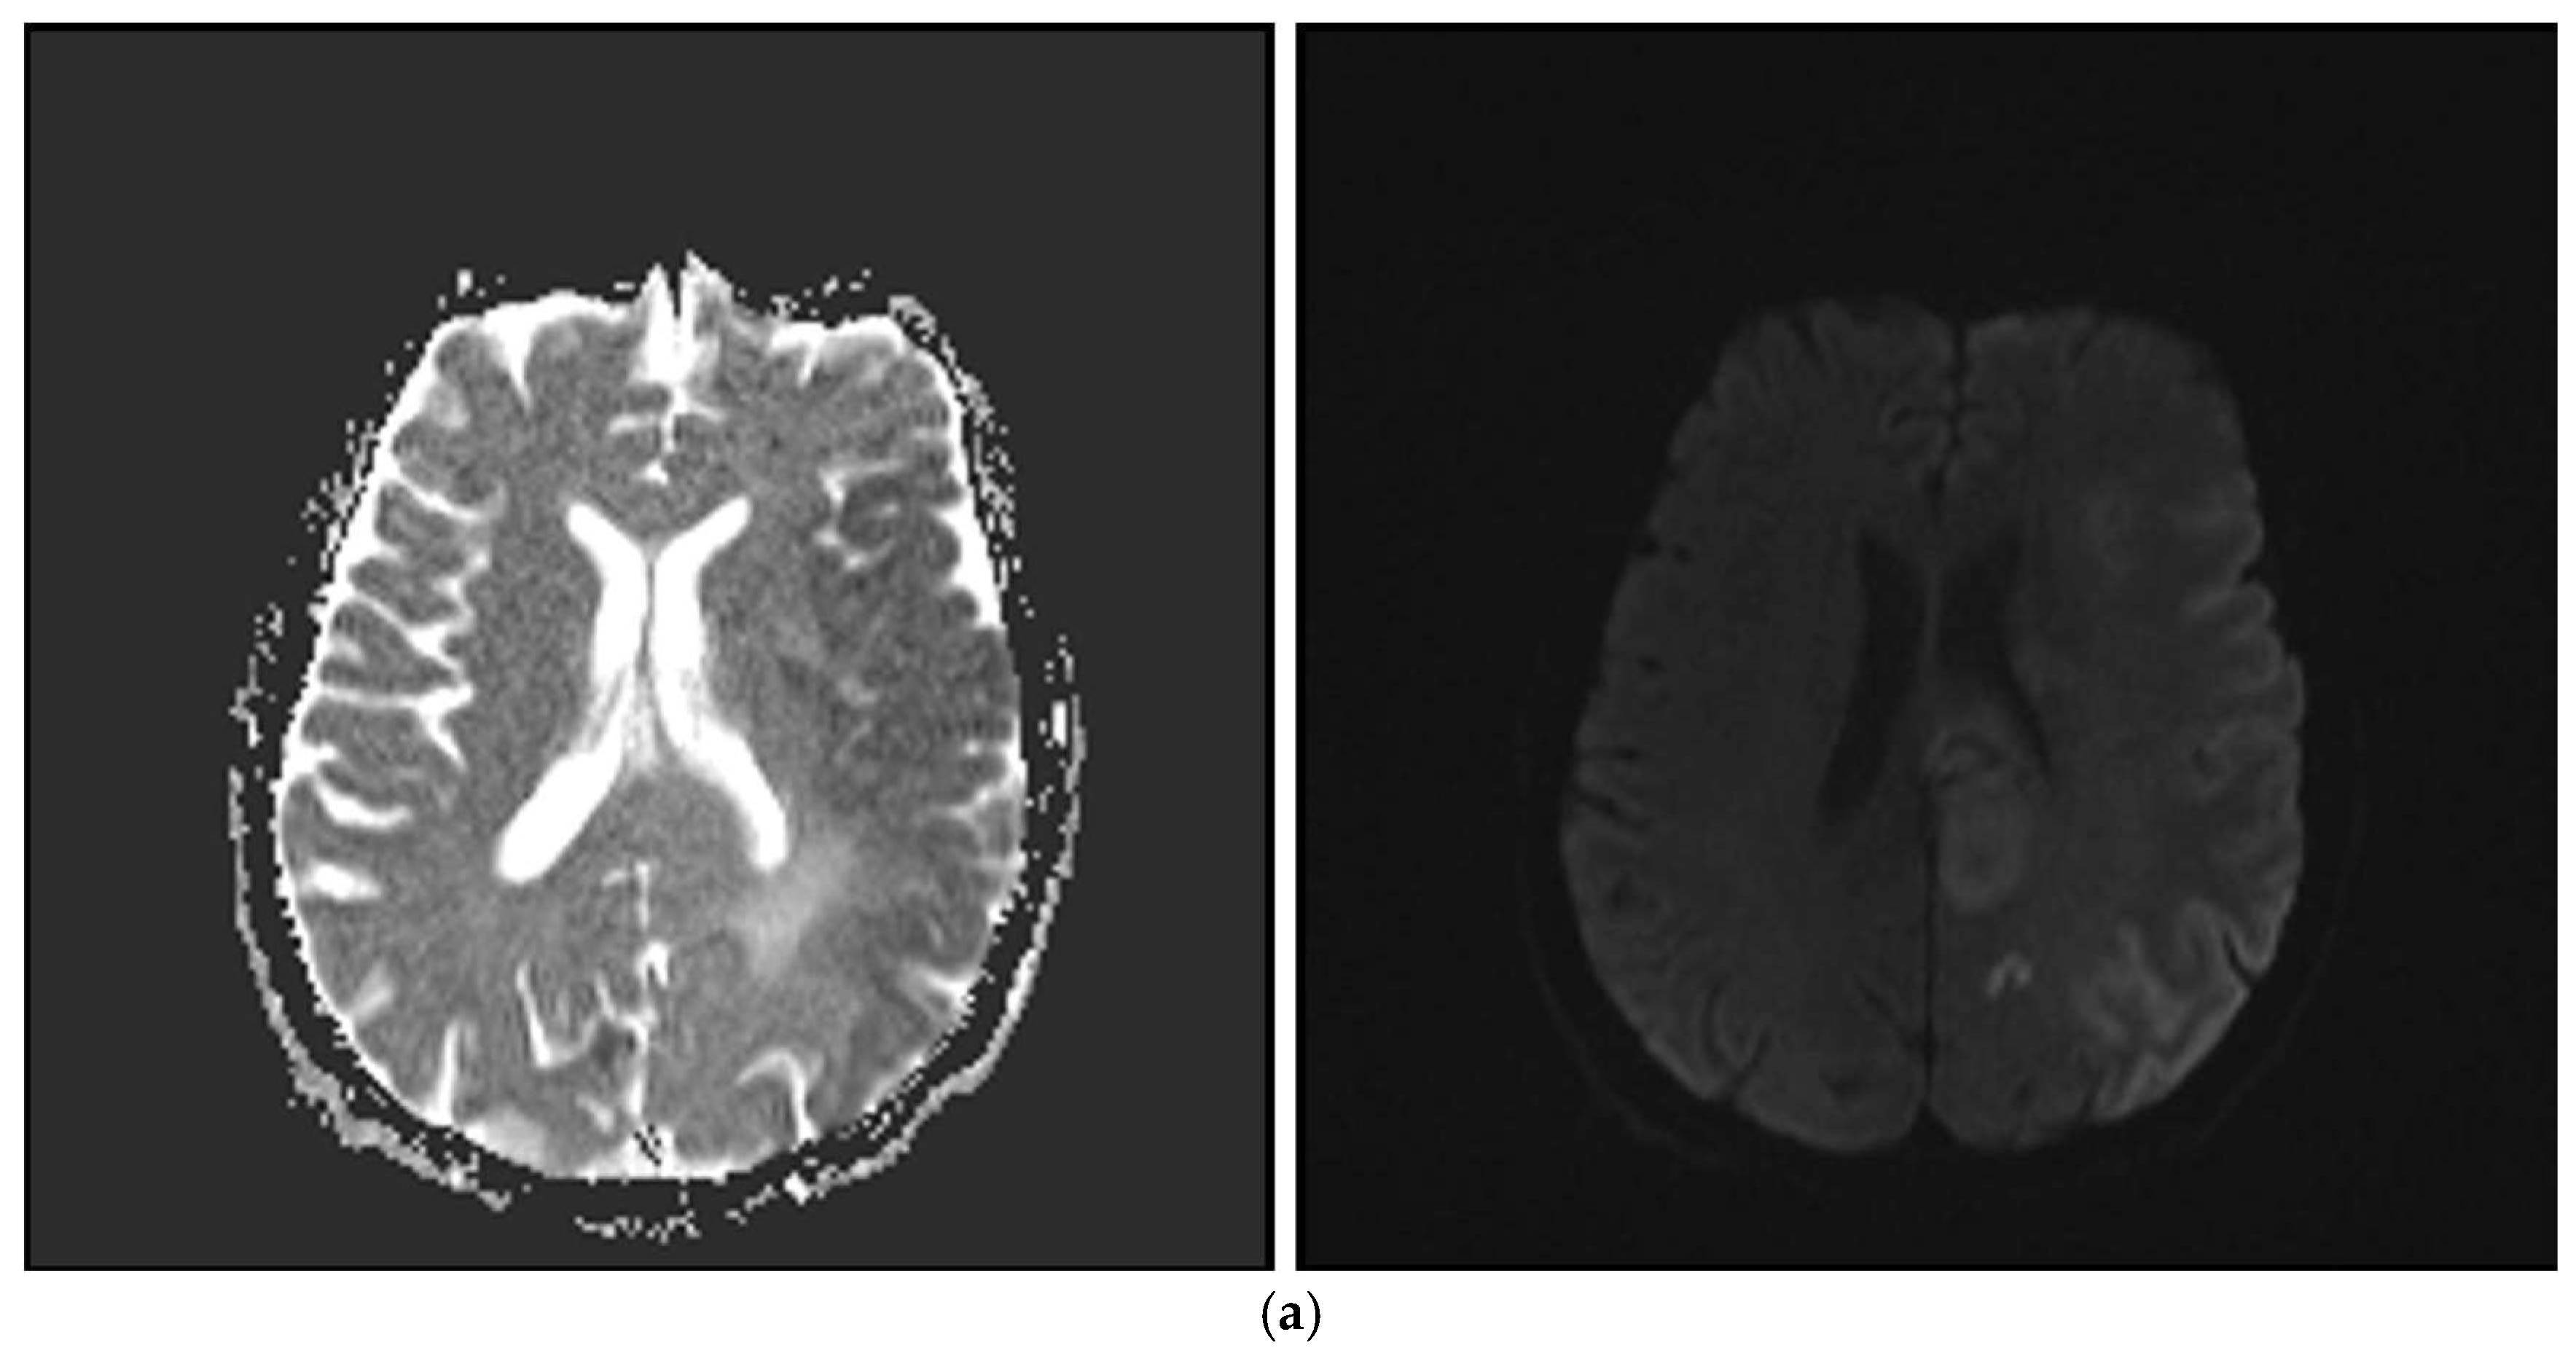

2.4. Imaging Protocol

| NIHSS scores | 11.1 (±4.7) |

| mRS scores | 4 (2–5) |

| Occlusion Location | |

| MCA M1 | 37 (64.9%) |

| ICA terminal | 11 (19.3%) |

| ICA proximal | 17 (29.8%) |

| ACA | 5 (8.8%) |

| Basilar artery | 2 (3.5%) |